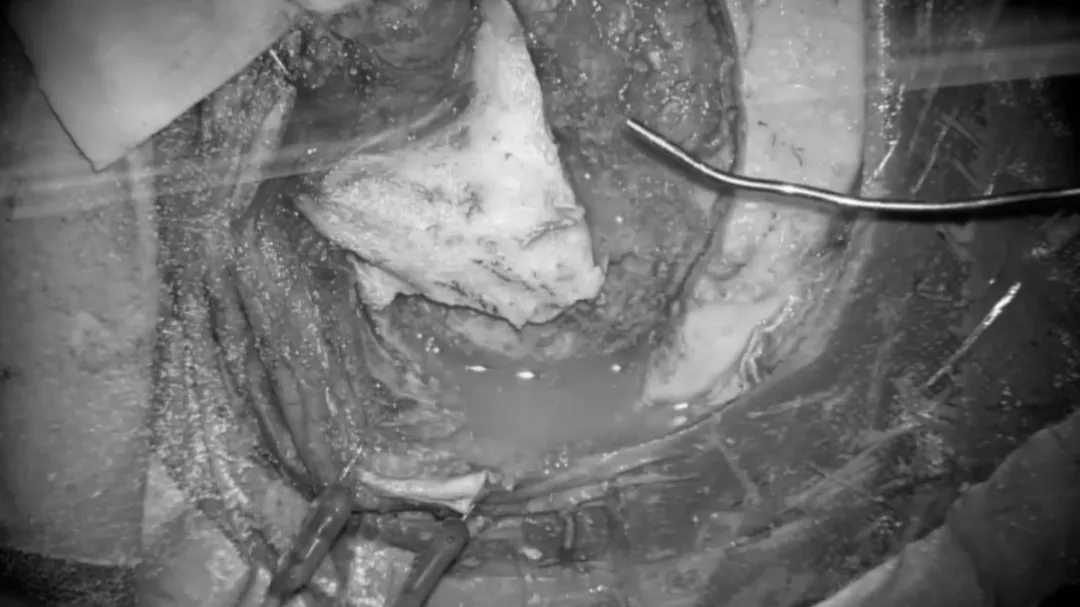

从肿瘤中分离、游离颅神经。使用显微镊来保留神经血管结构周围的蛛网膜平面。滑车神经在幕状韧带下方可见,使用CUSA刀进行逐步轻柔的肿瘤减压,这个操作对于保护位于这一重要区域的基底动脉穿支是非常重要的。

从病变中游离动脉穿支,在识别基底动脉后,使用低负压吸引器和显微剪逐渐移动肿瘤,将肿瘤从这些血管中分离揭牌。这种精细的操作是在高倍放大的显微镜下进行的,以便安全地分离蛛网膜和切断肿瘤的基底动脉及其穿支。

肿瘤的背侧表面也使用相同的技术进行解剖、分离。在脑干水肿和肿瘤紧密粘连于脑干的情况下,部分肿瘤残端需考虑保留,以避免损伤这些穿支。

第三对颅神经的识别。逐渐地,动眼神经被识别并从肿瘤中分离,同时沿着Dorello’s管方向分离解剖及保护外展神经。